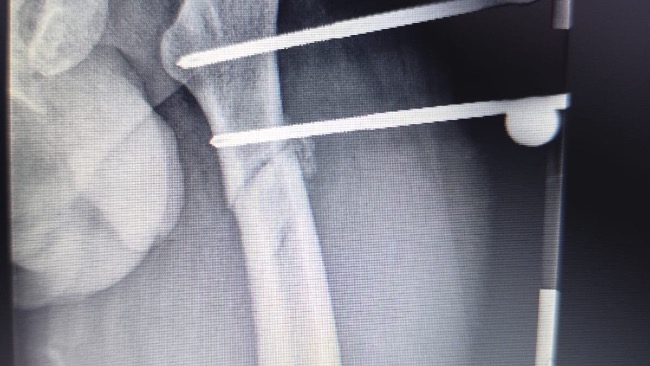

Na miejsce przyleciał śmigłowiec ratunkowy, który zabrał go do szpitala w Olsztynie. Tam rozpoczęła się dramatyczna walka o jego życie. Tata miał zmiażdżone obie nogi, wieloodłamowe złamania obu kości udowych, duży ubytek mięśni i tkanek w lewej nodze, liczne złamania miednicy oraz poważne uszkodzenia narządów wewnętrznych. Lekarze musieli natychmiast operować. Trafił na oddział intensywnej terapii i został wprowadzony w śpiączkę farmakologiczną.

Po ponad miesiącu hospitalizacji tata wrócił do domu, ale jego walka wcale się nie skończyła. Do dziś ma w nodze zewnętrzny stabilizator, metalowy stelaż z prętów wychodzących z uda. Nie jest w stanie samodzielnie chodzić ani ustać na nogach. Porusza się na wózku. Przez długie unieruchomienie jego mięśnie bardzo osłabły, a niektóre zanikły.